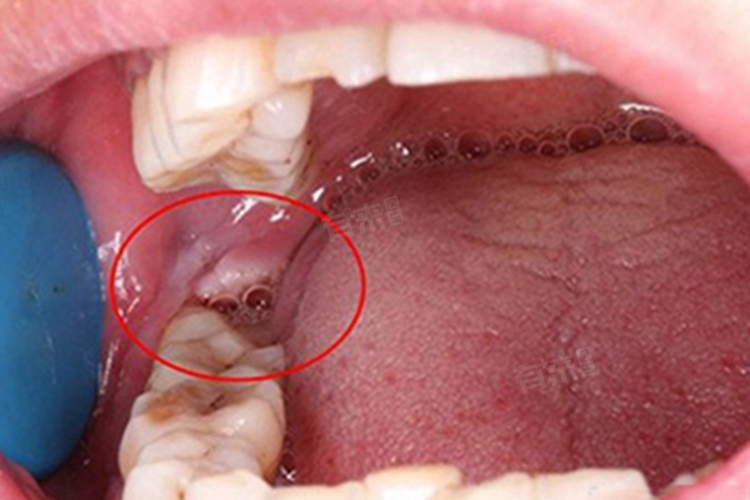

智齿牙洞很大很深会带来疼痛、影响咀嚼,还可能引发感染。遇到这种情况,应及时采取措施,包括药物治疗、充填治疗,甚至是拔牙治疗等。

2、充填治疗:当智齿牙洞很大很深,影响咀嚼且经常出现食物嵌顿,但未伤及牙髓神经时,可考虑充填治疗。医生会去除牙洞中的腐坏组织,再使用合适的材料进行充填,从而恢复牙齿的完整性和功能。

3、根管治疗:若牙洞已经深入牙髓腔,引起牙髓炎或根尖周炎,需要进行根管治疗。医生会清除感染的牙髓组织,进行根管消毒和充填,以保留患牙并恢复其功能。

4、拔牙治疗:如果智齿牙洞很大很深且伤及牙髓神经,或者智齿位置不正、无咬合功能、治疗困难,建议及时拔牙。避免炎症扩散到周围牙龈组织,造成不适。